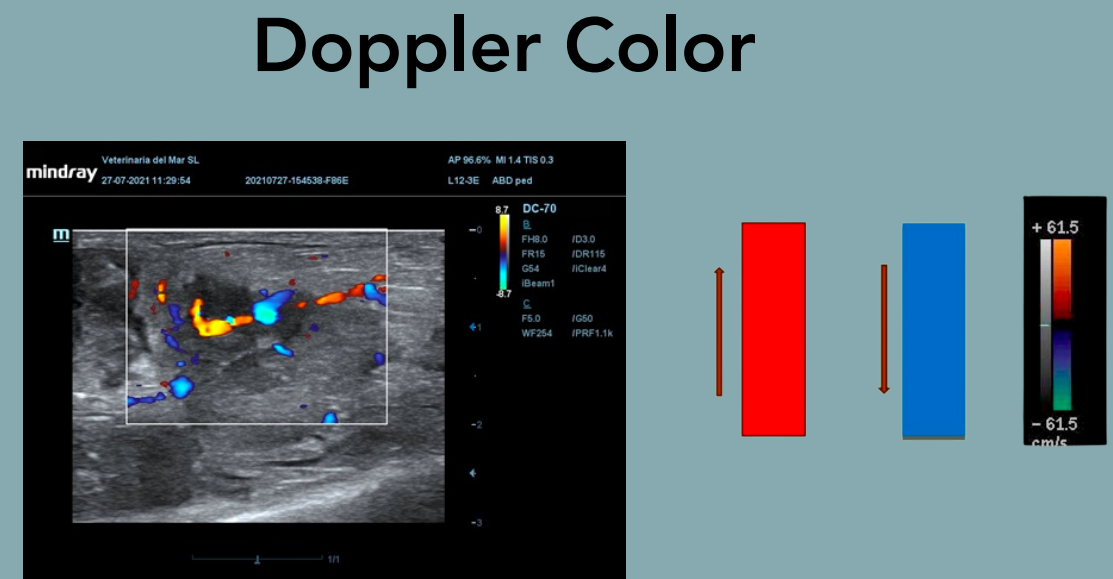

Doppler Color

Funcionamiento: Superpone la información Doppler en color sobre la imagen bidimensional (B-mode). Convenciones de color: Escala variable según ajustes.

-

Rojo: flujo hacia el transductor.

Azul: flujo alejándose. Ventajas: Visualización rápida y global del patrón de flujo. Detecta turbulencias y direcciones. Limitaciones: Menos sensible que el Doppler espectral y menos exactitud en velocidad.